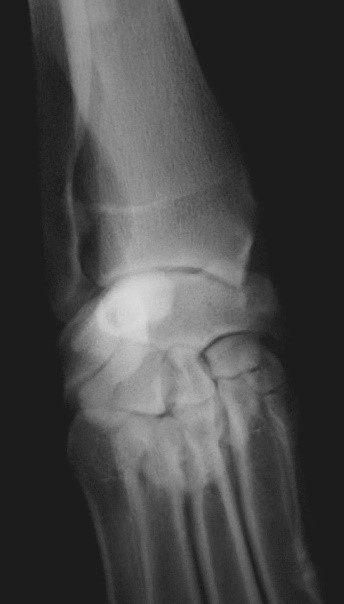

What does this show?

Normal carpus